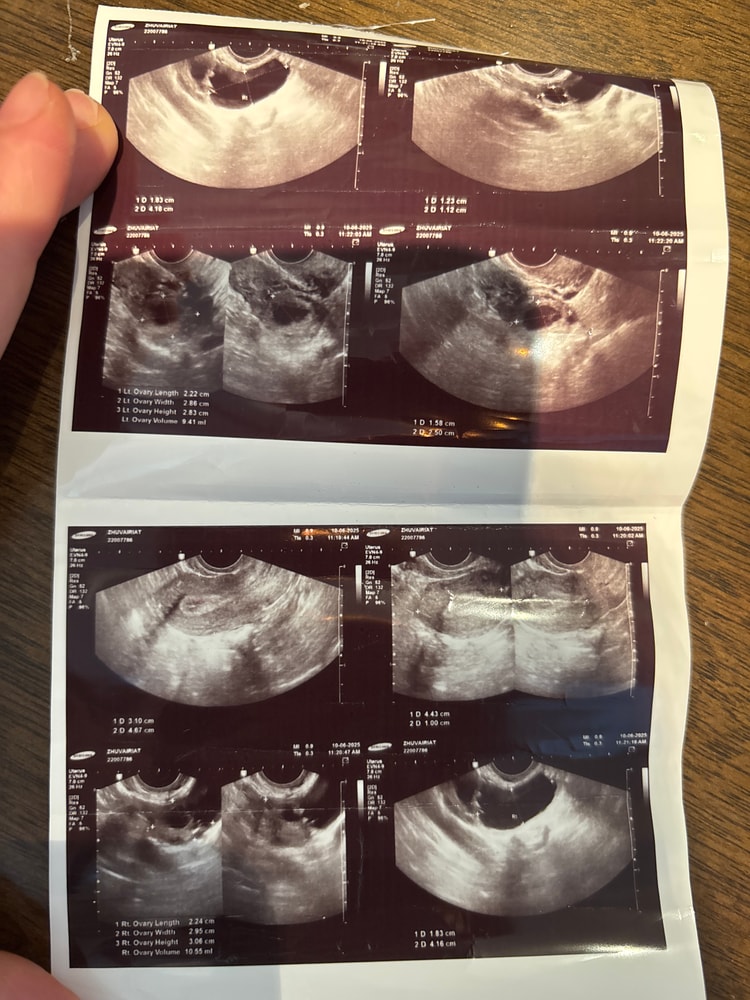

Изображение

Джамиля, ну похоже на жт, но мы же не узисты, поэтому не точно))🤷🏼‍♀️

Вы Же были у врача. Думаете мы тут лучше знаем. Если она не видит, то его нет. Возможно кистой переросло